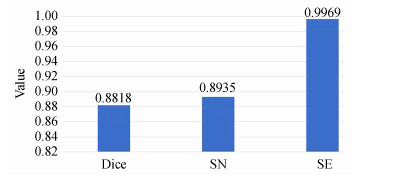

从图 11可知,结合实例归一化的方法其脑肿瘤检测网络的三种评价指标Dice、SN和SE可以达到0.881 8、0.893 5和0.996 9,较3.2.1节中的多模态脑肿瘤检测模型,Dice、SN两项指标各提升了3.92%和6.81%,而SE指标降低了0.02%.

图 11 结合实例归一化的脑肿瘤检测模型评价指标